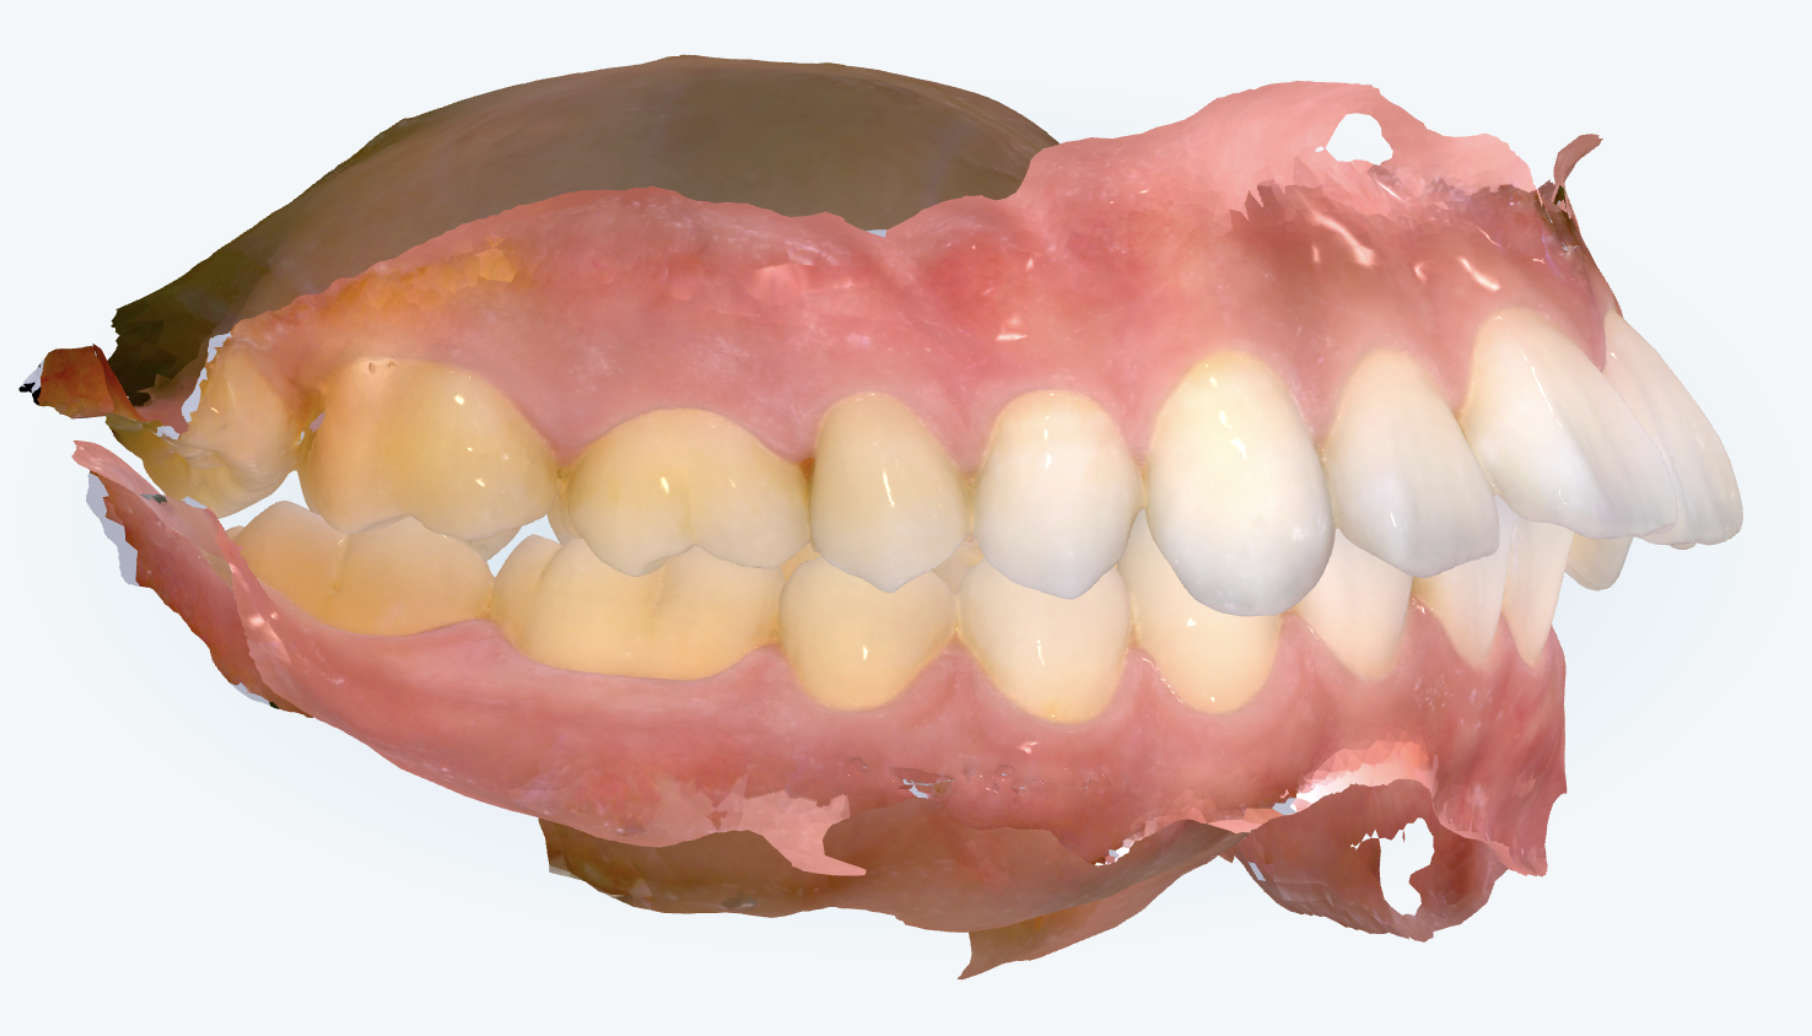

初診時の画像診断

前歯は上顎前突(いわゆる「出っ歯」)の傾向が見られ、歯列全体がV字状にやや前方へ尖っているアーチをしています。前歯の傾斜角は前方への傾きが顕著でした。

また、奥歯のかみ合わせにもズレが見られ、上顎歯列全体が前に位置していることが根本的な原因と考えられました。